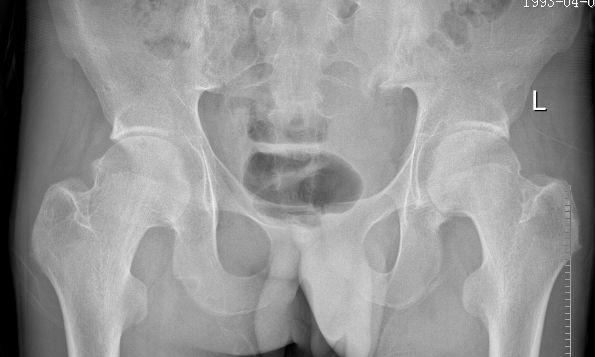

例1:21岁男性,AS患者,双髋关节疼痛伴活动受限4年